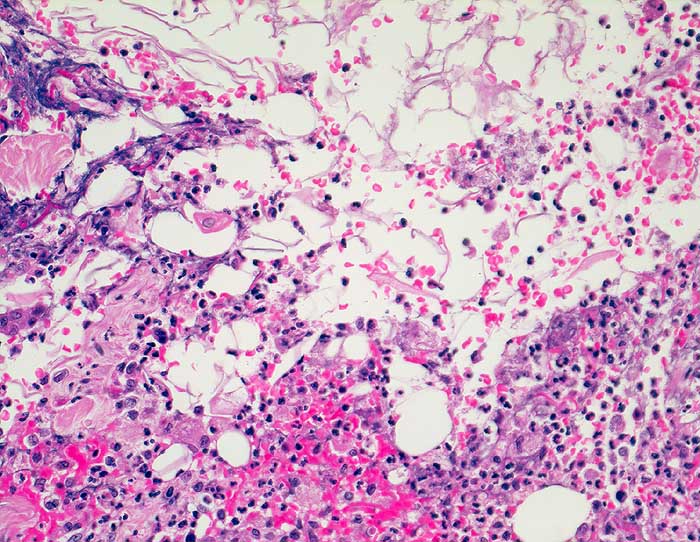

Rupturierte Epidermoidzyste

Die Zystenwand ist vollständig entzündlich zerstört. Das Entzündungsinfiltrat besteht aus Granulozyten und Histiozyten durchmischt mit Blut. In der oberen Bildhälfte sind zahlreiche Hornlamellen erkennbar.

Grosses, seit 5 Jahren bestehendes, entzündlich verändertes Atherom am Rücken